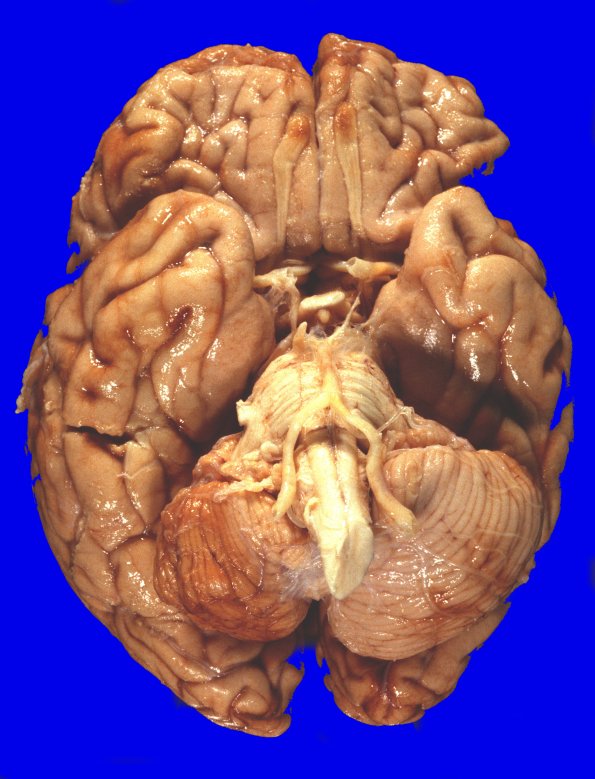

25A1,2 At autopsy the weight of the unfixed brain was 1240g. There are numerous foci of orange-brown discoloration and surface granularity involving the tips of the occipital lobes, the right cerebellum, anterior frontal lobes, particularly the inferior orbital aspects and involving the olfactory bulbs, as well as the lower lateral aspects of the frontoparietal cortices bilaterally. The right cerebellar hemisphere is markedly shrunken, particularly the superior aspect. All the hemorrhagic lesions were thought to represent contusions.